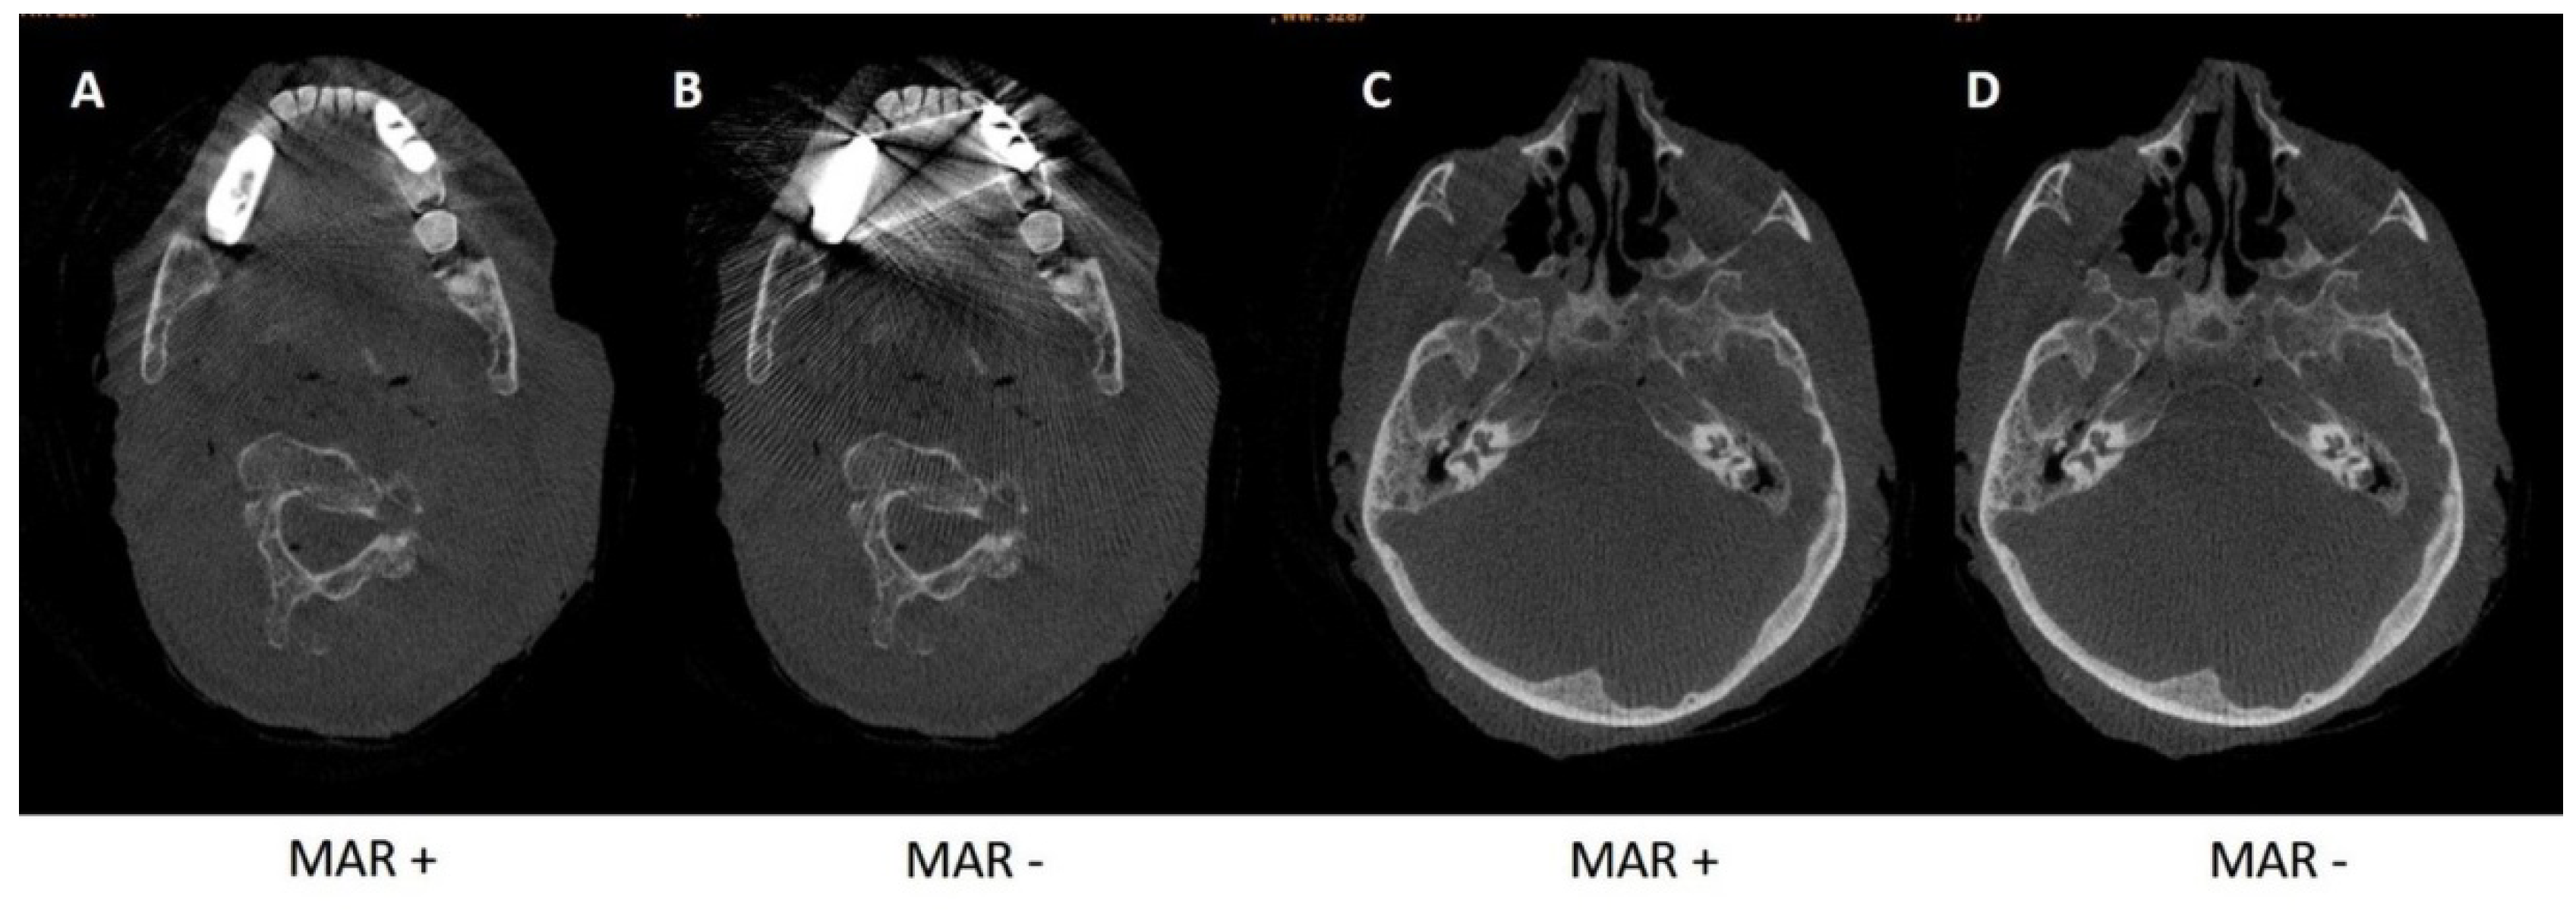

3.1.2. Metal Artifact Reduction Algorithm